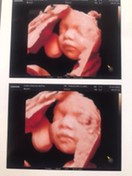

กำหนดคลอด 22 พ.ค GA 27+3 wks

แม่ๆไปซาวน์กันมารึยังคะ น้ำหนักเท่าไหร่กันแล้ว ส่วนตัวแม่ขึ้นมา 12 โลแล้ว นน. ลูกตอนนี้ 1,090 กรัม

บ้านนี้27+3น้ำหนักขึ้นมาครึ่งโล น้ำหนักลูก1355กรัม😍😍

บ้านนี้ขึ้นมา 6 โล ซาวด์ตอน 27+3 น้องหนัก 1112 จร้า ♥️